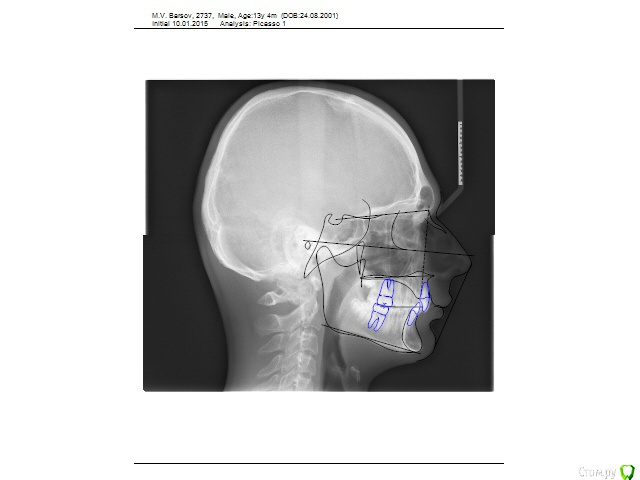

Dvoe Опубликовано 30 января, 2015 Поделиться Опубликовано 30 января, 2015 Добрый день! Планируем установить брекеты подростку 13 лет.Сделали снимки с расчетами, врач говорит о необходимости удаления двух верхних 5-к.... процесс удаления здоровых зубов волнителен. Обоновано ли это удаление? Ссылка на комментарий

Yana guapa Опубликовано 30 января, 2015 Поделиться Опубликовано 30 января, 2015 Добрый день! Планируем установить брекеты подростку 13 лет.Сделали снимки с расчетами, врач говорит о необходимости удаления двух верхних 5-к.... процесс удаления здоровых зубов волнителен. Обоновано ли это удаление? Хотелось бы все-таки получить чуть больше информации. (прочитайте в "правилах форума) И снимки, и фото, и, конечно же, жалобы. Почему решили лечиться. Но даже по этому снимку можно предположить, что удаление здесь не показано. Ссылка на комментарий